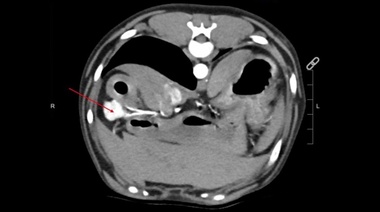

Oncología veterinaria

Feocromocitoma canino: un estudio revela razas y factores de riesgo

16/10 | El primer estudio poblacional sobre feocromocitoma en perros reveló razas predispuestas y factores de riesgo, brindando a los veterinarios herramientas para su detección temprana. Este tumor endocrino suele pasar inadvertido por sus signos clínicos inespecíficos, como hipertensión, colapsos o arritmias.